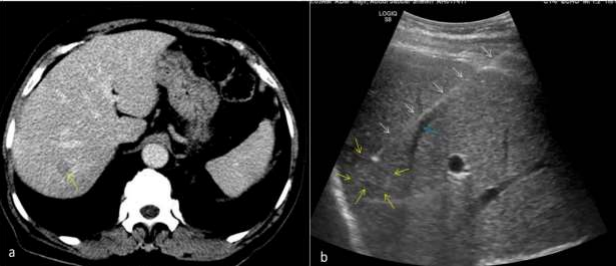

Figure 04: 69 Y / Male, operated case of carcinoma colon, on observation. Surveillance CT scan shows an irregular hypodense lesion in right lobe of liver (black arrow in a) and associated focal IHBR dilatation (yellow arrow in a). Correlative ultrasound shows an irregular hyperechoic lesion in right lobe of liver (black arrow in b). USG guided FNAC was done (c) with needle close to the branch of portal vein (white arrow in c) and is avoided.

Figure 05: 42Y/Female, known case of carcinoma breast with new onset 5 mm lesion in segment VIII of liver. Note the location of the lesion beneath the rib. Needle was inserted in this small lesion in breathhold during inspiration. White arrow denotes rib, red arrows denote the liver lesion and yellow arrow denotes the spinal needle with its tip inside the liver lesion. Background liver shows fatty infiltration. Cytology report suggestive of reactive atypia in the liver lesion.